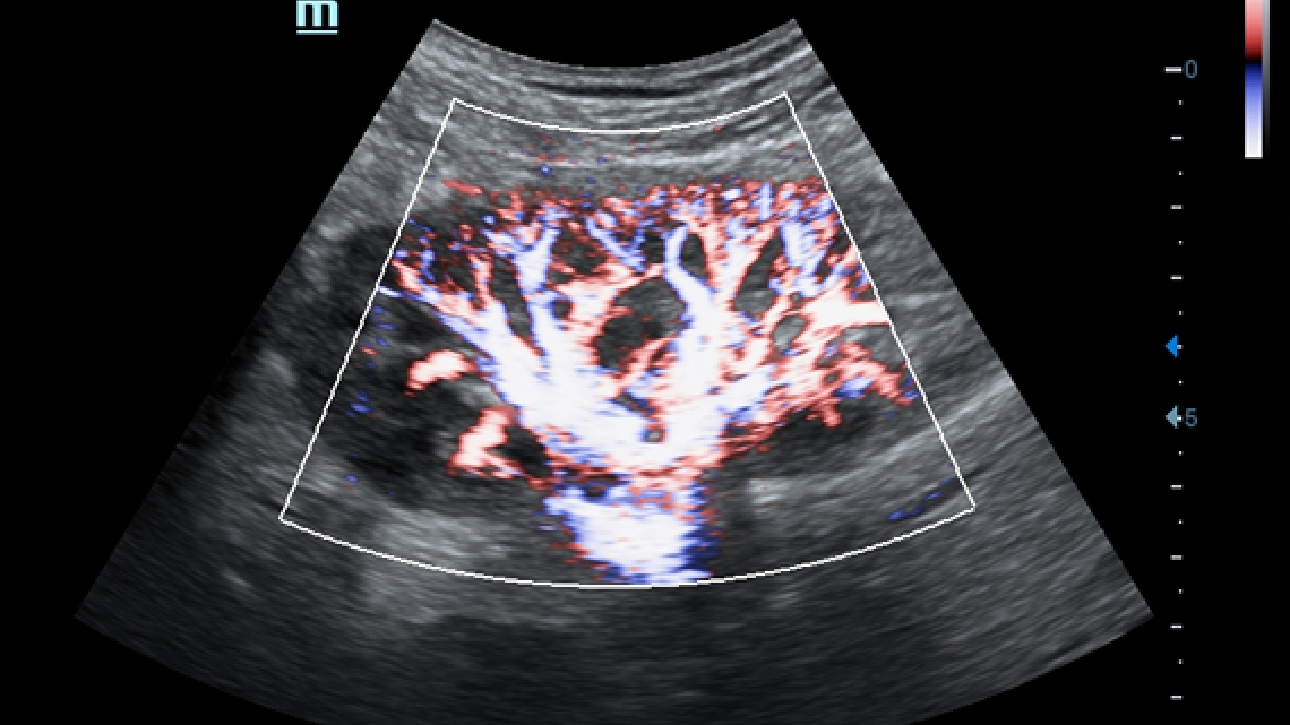

X-Insight es la soluci├│n intuitiva para una mejor visualizaci├│n.

La nueva soluci├│n de Mindray es una excelente transformaci├│n desde la continua comprensi├│n de las necesidades cl├Łnicas del usuario, combinada con la evoluci├│n de la tecnolog├Ła de los ultrasonidos m├Īs puntera. Repleto de vitalidad, con el ├║nico objetivo de visualizar el futuro y evitar los l├Łmites, el ec├│grafo DC-60Exp con X-Insight est├Ī constantemente mejorando con una escalabilidad aumentada. Como un socio personal, el equipo de ultrasonidos DC-60 Exp con X-Insight se centra en lo que verdaderamente importa, ayudando al usuario a administrar su pr├Īctica cl├Łnica con facilidad y seguridad.

Bas├Īndose en una profunda comprensi├│n de las necesidades del usuario, el sistema de ultrasonidos DC-60 Exp con X-Insight est├Ī dise?ado para ofrecer una alta eficiencia con im├Īgenes de precisi├│n, la cual se ve potenciada por una claridad inmediata, una inteligencia excepcional y benefici├Īndose de una c├│moda experiencia.